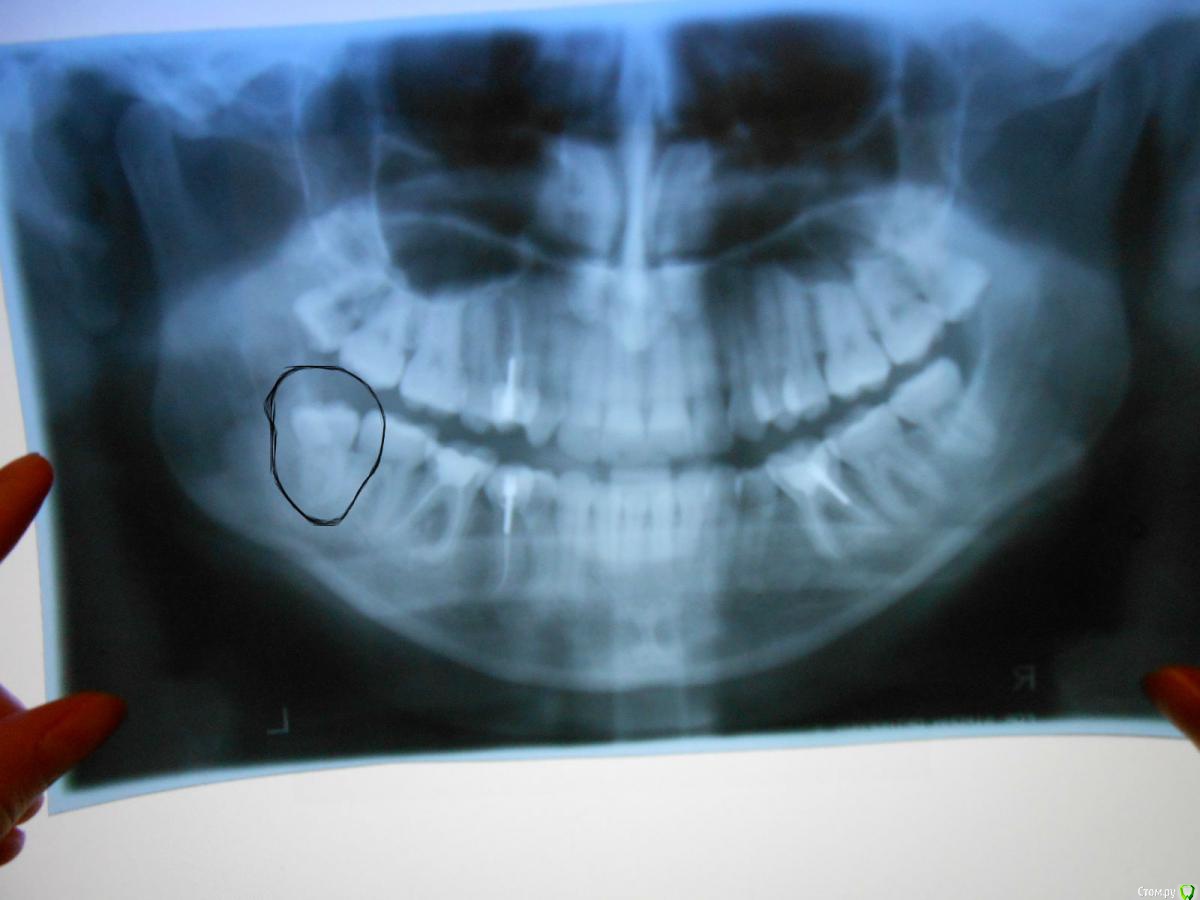

Ольга1991 Опубликовано 7 октября, 2015 Поделиться Опубликовано 7 октября, 2015 Здравствуйте, Уважаемые Доктора!Уже задавала вопрос про удаление в разделе "хирургия", но пока искала врача, задумалась, а стоит ли вообще трогать этот зуб? В перспективе планирую ставить брекет-систему. В пятёрке и шестёрке со стороны проблемного зуба удалены нервы. Что, если один из них удалить, а на его место подвинуть за ним стоящие, в том числе и восьмёрку? Возможно ли такое? Можно ли её каким-либо образом заставить вылезти в нужном направлении?( волнующий зуб отмечен на снимке)Заранее благодарю. Ссылка на комментарий

колесников Опубликовано 7 октября, 2015 Поделиться Опубликовано 7 октября, 2015 У вас имеется патология прикуса, я так понимаю, на снимке видна скученность в области премоляров. Ортодонтическое лечение вам показано. И перемещать зубы в вашем случае лучше не сзади наперёд ,а в обратном направлении. Если коротко: обратитесь к ортодонту.вероятнее всего ,перед лечением,вам предложат удалить 48ой и 1-2 премоляра. Есть вопрос к 46ому. Вопросы лучше задавать лечащему врачу. 1 Ссылка на комментарий